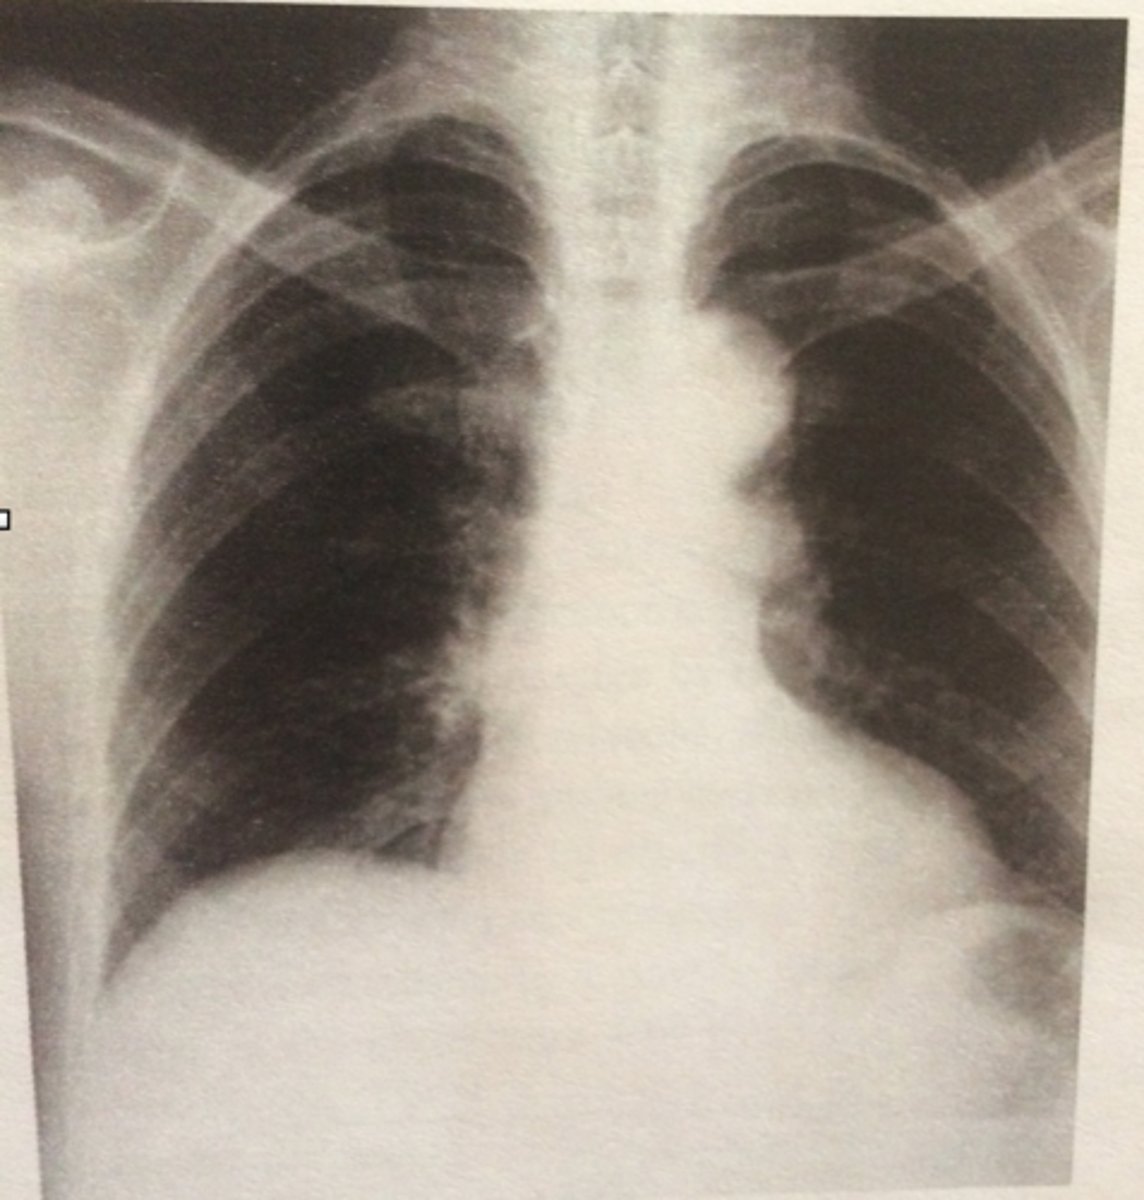

Diaphragm